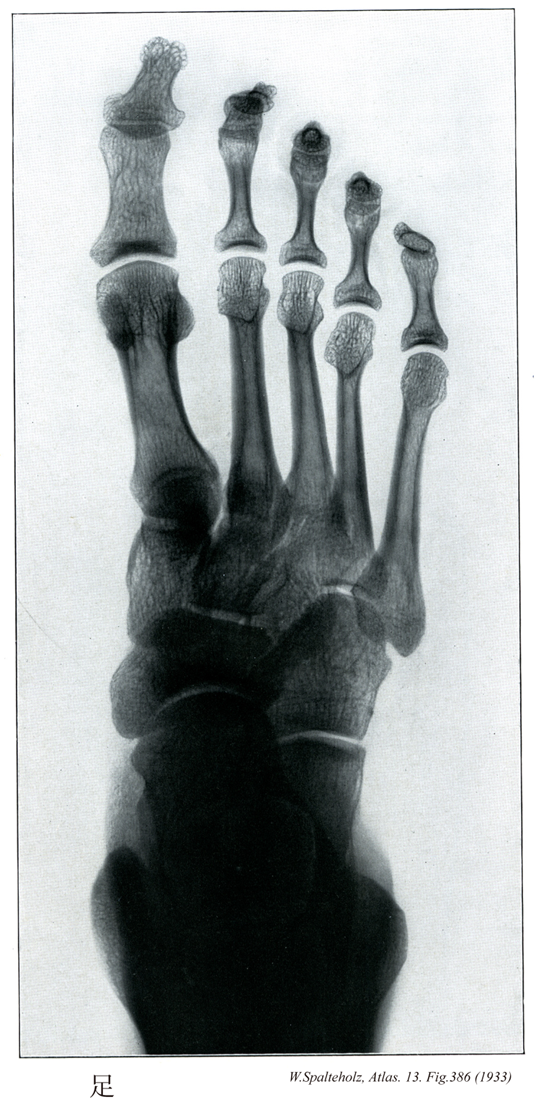

386